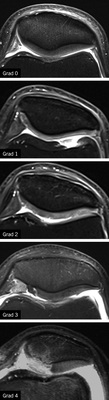

Grading der Knorpelveränderungen im MRT

Für die Graduierung der Ausprägung von Knorpelläsionen existieren unterschiedliche Klassifikationen, die sich meist nur in Details unterscheiden und sich an der arthroskopischen Outerbridge-Klassifikation (1961) orientieren.

Für die Begutachtung der Knorpelläsionen im Rahmen der BK 2112 wird von der Konsensusarbeitsgruppe der DGUV (2014) empfohlen, die Einteilung nach Vallotton et al. (1995) zu nutzen (  Tabelle 4 ,   Abb. 8 ).

Diese ist in diesem Szenario vor dem Hintergrund von Bedeu-tung, wenn eine atrophe Form der Arthrose vorliegt, die keine oder nur geringe osteophytäre Anbauten zeigt, aber eine relevante Gelenkspaltverschmälerung vorliegt oder es um Fälle geht, die rein konventionell röntgenologisch nicht sicher einzustufen sind. Die Konsensusarbeitsgruppe zur BK 2112 fordert hier zur Anerkennung einer Gonarthrose Knorpelschäden, die mindestens einen Grad 3 oder 4 nach Vallotton erreichen sowie eine großflächige Ausdehnung innerhalb der betroffenen gegenüber artikulierenden Gelenkflächen des betroffenen Kompartimentes (2014).